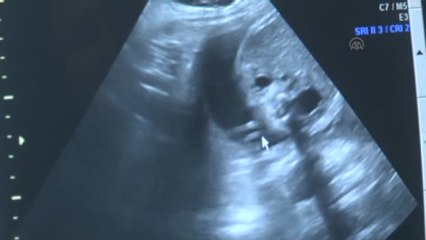

Yaklaşık 4 ay önce testinin pozitif çıkmasının ardından evinde tedavi süreci başlayan Faruk Çendek, durumunun ağırlaşması üzerine hastaneye başvurdu.